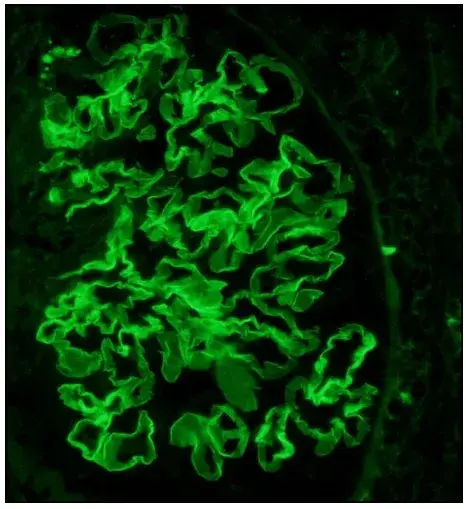

Uma causa incomum de hematúria glomerular intermitente!

Uma causa incomum de hematúria glomerular intermitente!

Hematúria pós infecção, caso clínicos para auxiliar no entendimento de causas glomerulares comuns e raras...